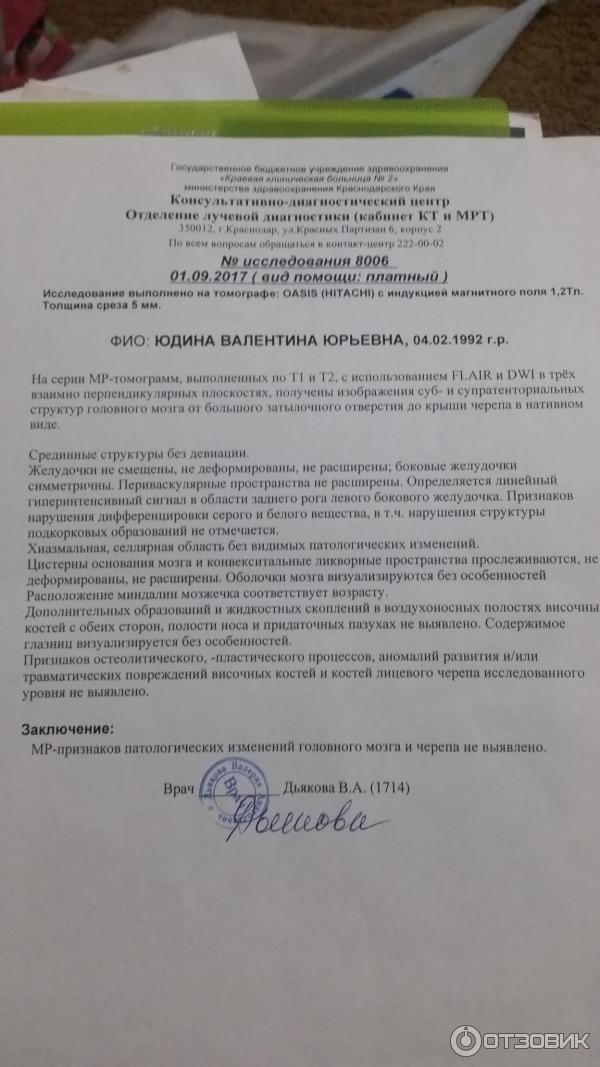

МРТ головного мозга: Расшифровка снимков и Интерпретация

Раздел: Визуальные уроки